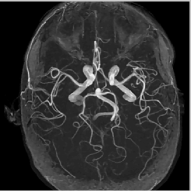

The reconstructions of a 256×256256256256\times 256 brain image from its radial samples acquired with a 40 spoke trajectory are shown in Fig. 6. The measurements are corrupted with zero mean complex Gaussian noise of standard deviation σ=18.8𝜎18.8\sigma=18.8. All methods result in loss of subtle image features since the acceleration factor and the noise level are high. We observe that the NLS scheme provides better recovery than the competing methods. The quantitative results in this setting for various MR images are shown in the bottom section of Table IV. We observe that the SNR improvement offered by NLS over the other methods are not as high as in the previous cases, mainly due to the considerable noise in the data and the high acceleration.

Refer to caption

(a) Original

(b) DLMRI,SNR=17.46

(c) TV,SNR=17.43

(d) NLS,SNR=18.46

(e) Sampling pattern

(f) DLMRI error

(g) TV error

(h) NLS error

Figure 6: Comparison of the algorithms in the presence of noise. We consider the recovery of a 256×256256256256\times 256 original MRI brain image from its radial trajectory with 40 spokes, contaminated by Gaussian noise with standard deviation σ=18.8𝜎18.8\sigma=18.8. The error images are magnified by a scale of 5 fold for the best visibility. This is a challenging case due to the high undersampling factor and high measurement noise. We observe that the NLS scheme provides the best overall reconstructions.